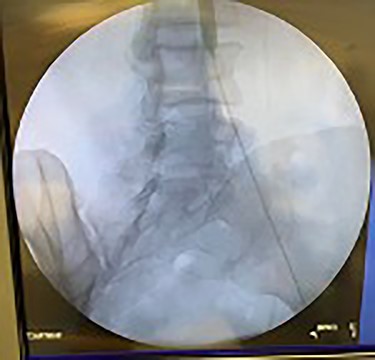

Catheter arteriogram results showed significant occlusion of the left iliac artery (Figs 3 and 4), the right iliac artery (Fig. 1), as well as the distal abdominal aorta (Fig. 2). There were numerous collateral vessels noted, indicating the presence of long-standing proximal stenosis (Fig. 1). The decision was made to use angioplasty to help widen the areas of stenosis. An 8 mm × 40 mm Passeo balloon was advanced from the right femoral artery into the left iliac artery (Fig. 7) and insufflated to 6 mmHg (Fig. 6). The balloon was allowed to remain expanded for 1 min and then was deflated. Next, the distal aorta was repaired in a similar fashion. The balloon was advanced into the distal aorta from the right femoral access and insufflated to 12 mmHg (Fig. 8). The balloon was allowed to remain expanded for 90 s.

Fluoroscopy of bilateral iliac arteries showing significant arterial disease.